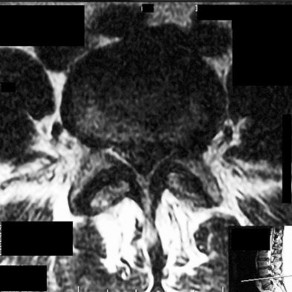

A 42-year-old male presents with severe lower back pain, bilateral sciatica, and new-onset urinary retention (post-void residual greater than 500 mL). MRI confirms a massive L4-L5 central disc herniation. Current literature suggests that surgical decompression is ideally performed within what timeframe to maximize the chance of urologic recovery?

Options:

- 6 hours

- 12 hours

- 24 hours

- 48 hours

- 72 hours

Correct Answer: 48 hours

Explanation:

Cauda equina syndrome is a surgical emergency. Meta-analyses (e.g., Ahn et al.) suggest that decompression within 48 hours provides significantly better outcomes for the return of normal motor, sensory, and urologic function compared to decompression performed after 48 hours.